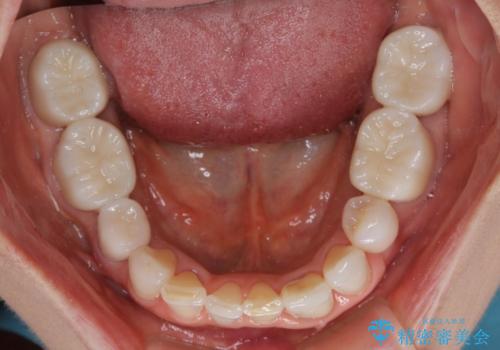

- 中学生の時にスポーツで折ってしまった前歯が変色してしまったとのことで来院された患者様です。

結婚式に向けてオールセラミッククラウンにて仕上げていくこととしました。